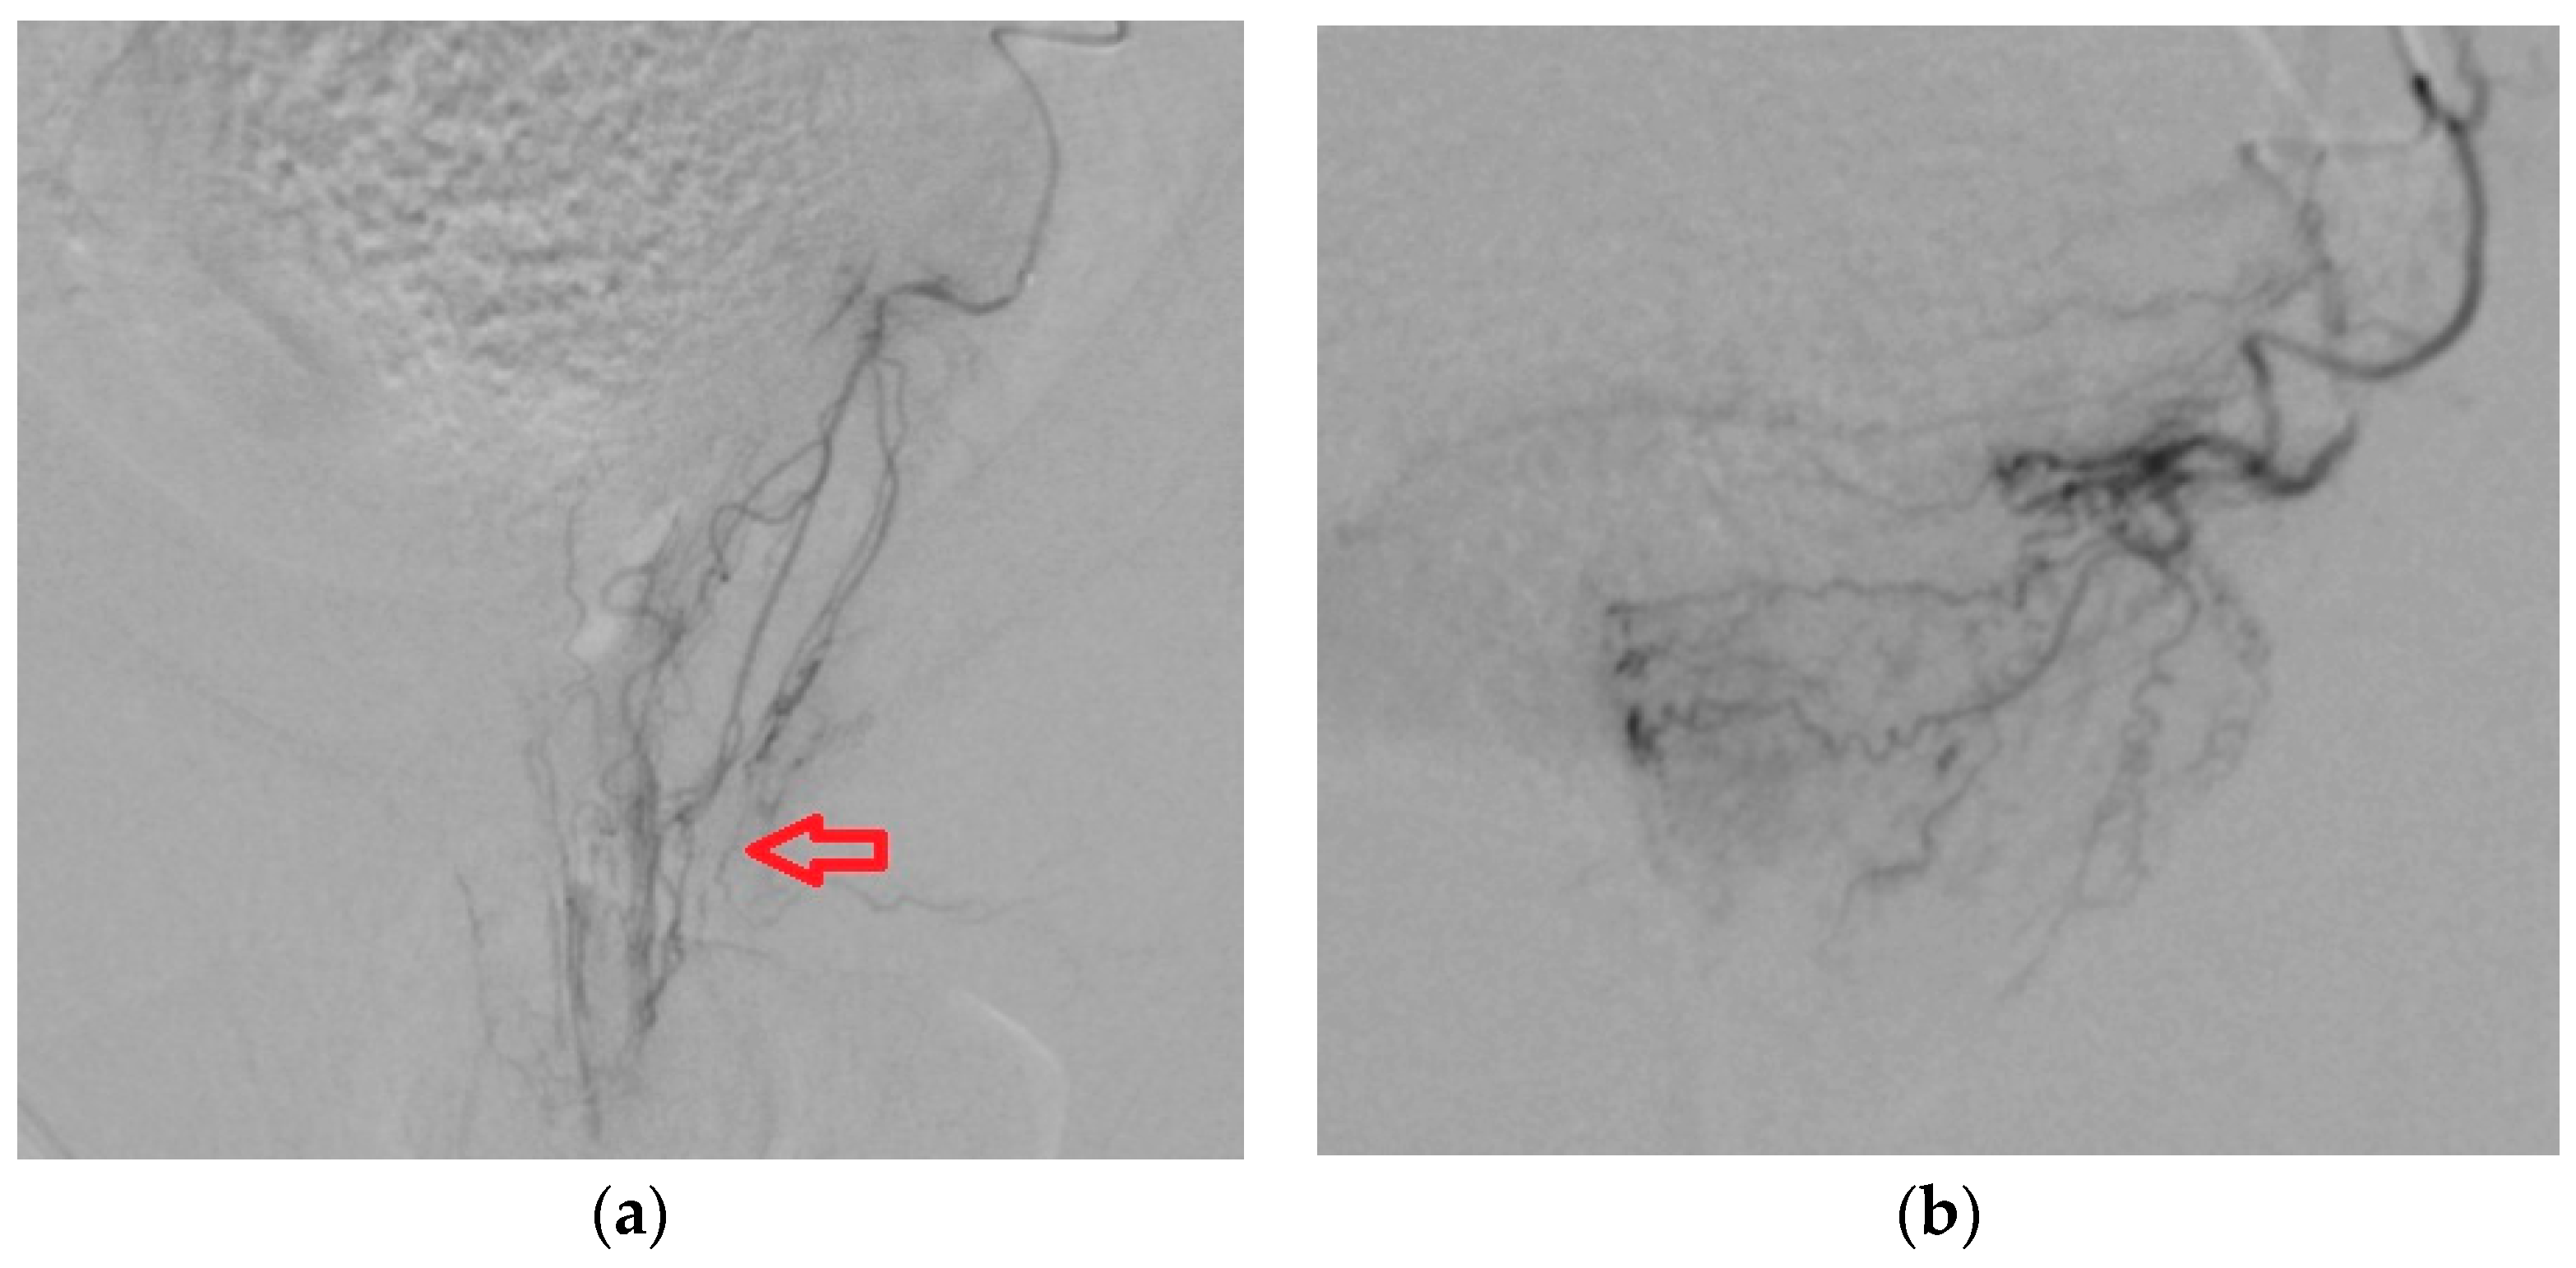

3.2. Importance of Supra-Selective Catheterization in Case of PA with Common Trunk or Anastomosis

3.2.1. PA origin with Common Trunk

3.2.2. Anastomoses of PA with Penile Artery